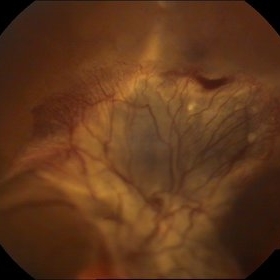

Traumatic Retinal Tear

Sep 10 2014 by Mehul A Shah

A myopic male patient 30-years-old presented to outdoor and found to have retinal detachment with giant tear following blunt trauma

Photographer: Drashti Netralaya,Dahod

Imaging device: FF 450

Condition/keywords: giant retinal tear